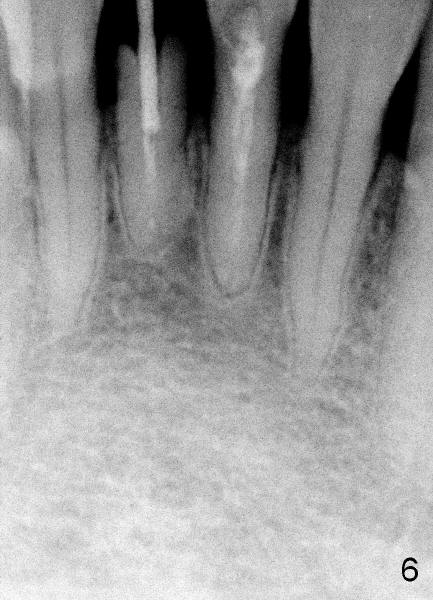

Dear Dr. Borgner: Thanks for the advice again. The patient showed up this afternoon. The tooth (in fact #25 in Fig.5) is pretty badly broken down, but the patient is not ready for implant right now. Prefabricated post and temporary crown are provided. Fig.6 shows the longest post space that can be gained. The mesiodistal dimension of the tooth is 3 mm above gingiva clinically; the buccolingual 5 mm; the minimal dimension between #24 and 26 is 3.5 mm. There is plenty of height. The longest one piece tapered implant from Tatum Surgical is 17 mm. The appropriate implant should be 3x17 or 3.5 x17 if the proximal surfaces of #24,26 are to be trimmed further. This was done when the temporary crown was fabricated. Anyway, thanks for guidance.